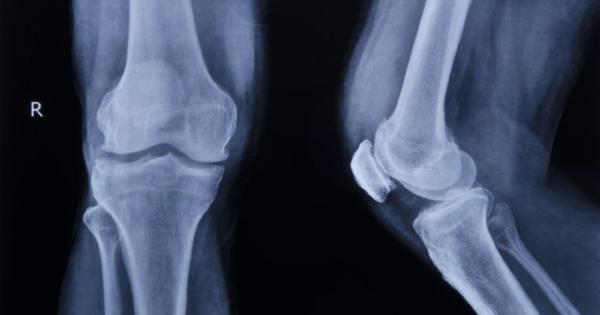

...... определяна едно „Тихата болест“. Остеопорозата е заболяване, което се характеризира с намаляване на масата на костното вещество и влошаване на костната тъкан, което преминава безсимптомно.

Остеопорозата е най разпространеното заболяване на костите То се характеризира с